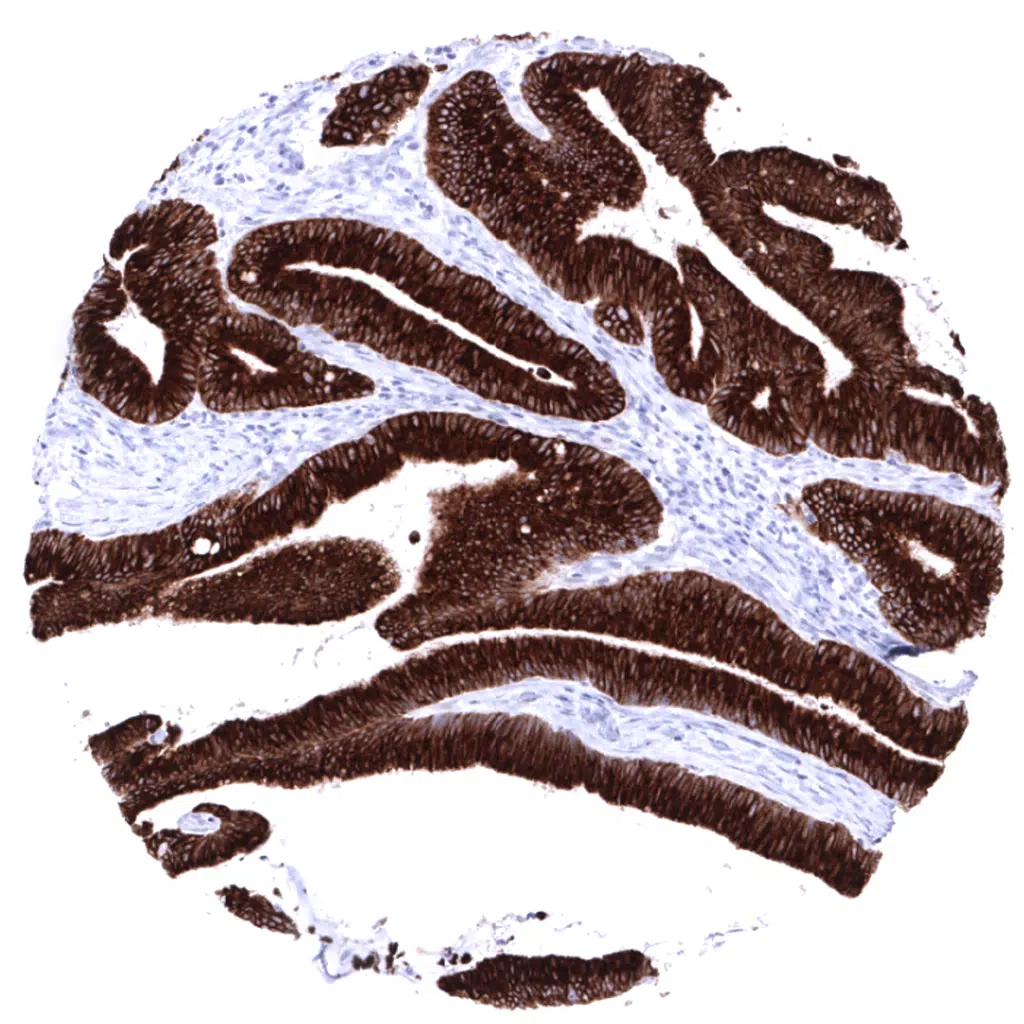

Colon- Strong diffuse MUC5AC positivity in a colorectal adenocarcinoma exhibiting an intestinal type growth pattern.